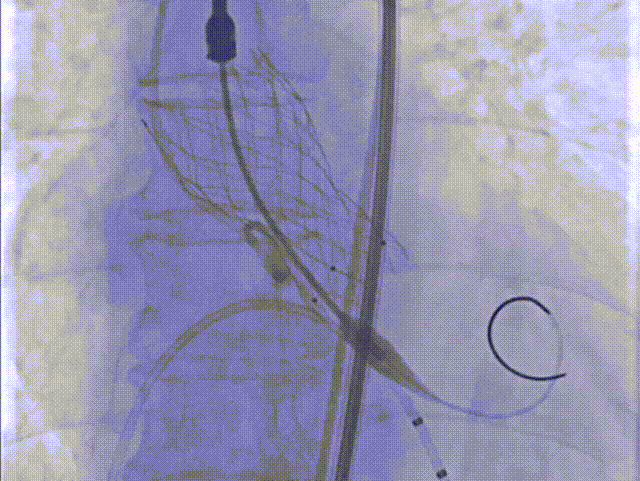

瓣膜定位

瓣膜释放过程

瓣膜形态

18球囊后扩张

瓣膜最终形态